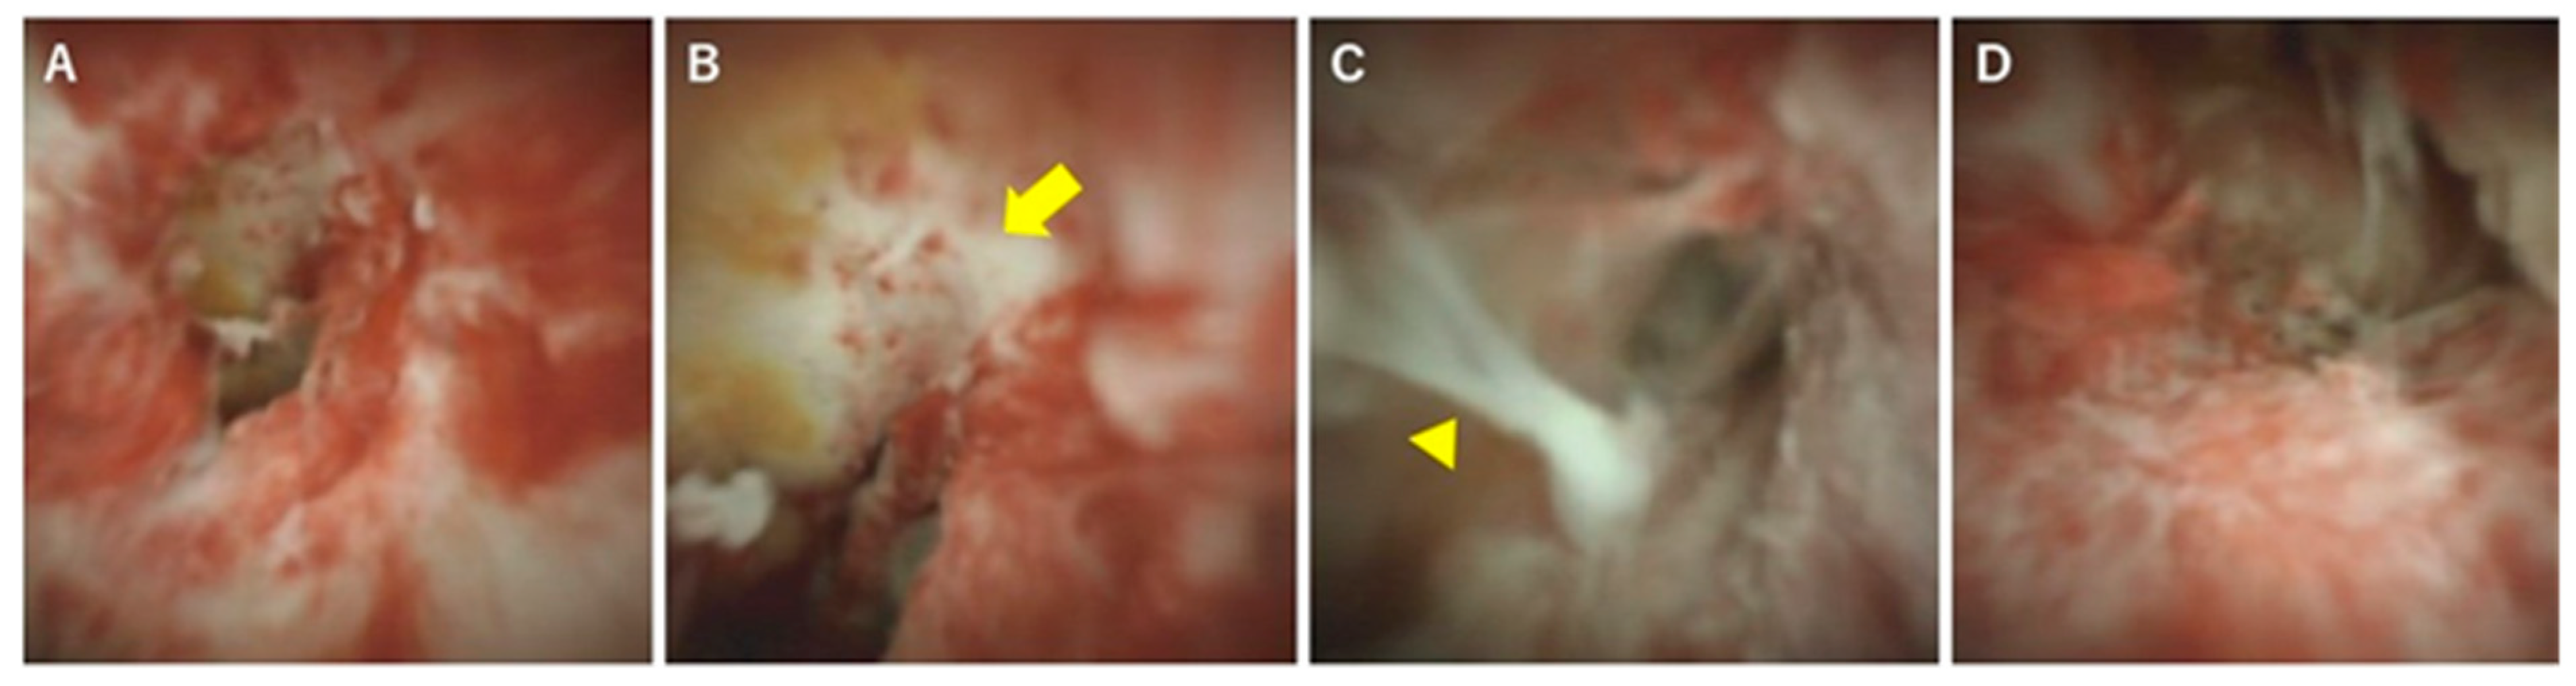

In terms of differentiation by appearance, Itoi et al. examined the usefulness of cholangiography for differentiating PSC, IgG4-SC, and cholangiocarcinoma [32]. They classified cholangioscopic findings into the following nine features: (1) mass formation, (2) bile duct stenosis, (3) dilated vessels, (4) tortuous vessels, (5) partially enlarged vessels, (6) irregular surface, (7) scarring, (8) pseudodiverticula, and (9) friability. As a result, scarring and pseudodiverticula were found to be characteristic findings of PSC, and partially enlarged vessels were characteristic of cholangiocarcinoma. The other findings of mass formation, dilated vessels, tortuous vessels, irregular surface, and friability were observed in both IgG4-SC and cholangiocarcinoma and were not helpful for distinguishing the two diseases. An irregular surface, although rare, was also observed in PSC. Sandha et al. further investigated the cholangioscopic findings of PSC and stratified PSC into the following three types based on visual characteristics: (1) inflammatory, (2) fibrostenotic, and (3) nodular or mass-forming. The inflammatory type showed mucosal erythema, ulceration, and fibrinous white exudate; the fibrostenotic type showed circumferential rings and asymmetric cicatrization; and the nodular or mass-forming type showed focal nodular tissue growth [33]. Although the small numbers of patients in both studies (five [32] and 29 [33] patients) might not accurately represent the overall disease characteristics of PSC, these results suggest that the cholangioscopic findings of PSC may vary according to the disease stage. Itoi et al. proposed that scarring and pseudodiverticula might only be indicative of the fibrostenotic type of PSC. The presence of the nodular or mass-forming type should signal the possibility of cholangiocarcinoma. We also experienced cholangiography in our PSC patients, and all of the findings, except partially enlarged vessels, were observed. Mucosal erythema (Figure 3A), ulceration (Figure 3B), fibrinous white exudate (Figure 3C), and irregular surface (Figure 3D) are often observed in active-phase patients with repeat acute cholangitis. These findings appear during the relatively early stages of PSC and might be classified as the inflammatory type, as proposed by Sandha et al. Patients with this type of PSC are also likely to have dilated vessels (Figure 4A), tortuous vessels (Figure 4B), friability (Figure 4C), and mass formation (Figure 4D). However, these findings are commonly observed in cholangiocarcinoma cases. On the other hand, scarring (Figure 5A), pseudodiverticula (Figure 5B), and bile duct stenosis (Figure 5C) are often observed in chronic-phase patients with a long history of PSC. Such patients might be classified as the fibrostenotic type. The finding of mass formation is sometimes observed in both the active and chronic phases of PSC. Since mass formation is difficult to distinguish from cholangiocarcinoma, it should be noted regardless of the phase. The time course of each phase and the characteristics of the different PSC types according to phase are summarized in Figure 6.

Figure 3. Cholangioscopic findings characteristic of the active phase of PSC. (A) Mucosal erythema, (B) ulceration (yellow arrow), (C) fibrinous white exudate (arrowhead), and (D) irregular surface. These findings are observed mainly during the active phase of PSC.